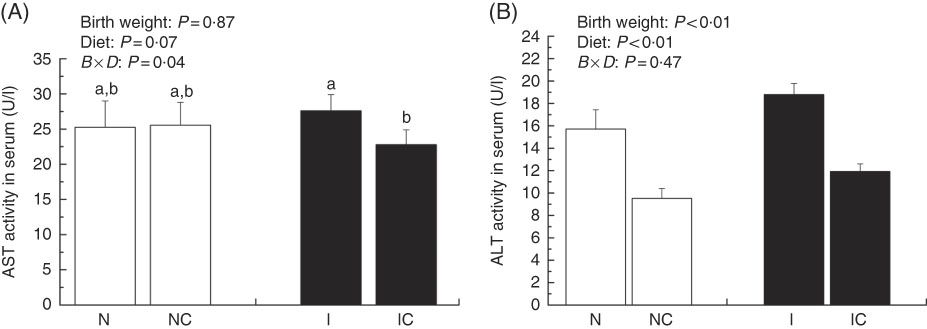

Activities of serum aspartate aminotransferase and alanine aminotransferase

The activity of serum AST was higher in the IUGR group (P>0·05) than in the NBW group (Fig. 3(A)). Dietary curcumin supplementation significantly decreased the activity of serum AST in the IUGR group (P<0·05). The activity of serum ALT was higher in the IUGR group than in the NBW group (P<0·05) (Fig. 3(B)). Because of dietary curcumin supplementation, the activity of ALT was significantly lower in the NC and IC groups than in the NBW and IUGR groups (P<0·01).

Fig. 3 Activities of aspartate aminotransferase (AST) (A) and alanine aminotransferase (ALT) (B) in the serum of normal birth weight rats (N), normal birth weight rats supplemented with curcumin (NC), intra-uterine growth retardation (IUGR) rats (I) and IUGR rats supplemented with curcumin (IC) (12 weeks of age). Values are means (n 6) and standard deviations. ![]() , Normal birth weight;

, Normal birth weight; ![]() , IUGR; B, birth weight; D, diet; B×D, interaction between the corresponding parameters. Data were analysed by using two-way ANOVA. a,b Mean values with unlike letters were significantly different when a significant interaction was observed (P<0·05).

, IUGR; B, birth weight; D, diet; B×D, interaction between the corresponding parameters. Data were analysed by using two-way ANOVA. a,b Mean values with unlike letters were significantly different when a significant interaction was observed (P<0·05).